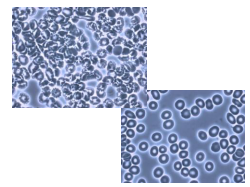

Though home for many bacterium

to surgery they don’t have to succumb

I dream that dentistry will finally discover

hundreds of microbes living under cover

Heart disease and even cancer

are not a normal healthy answer